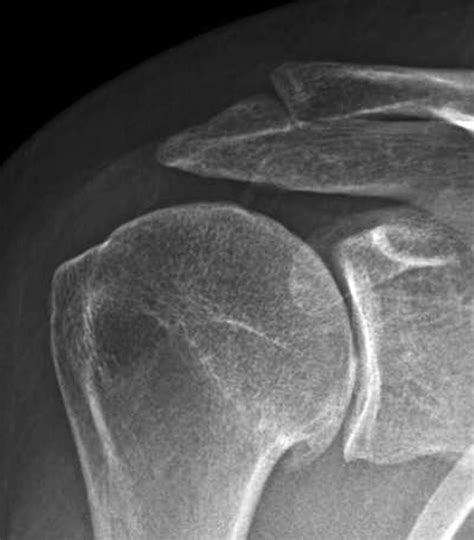

Diagnosing Post Traumatic Arthritis usually involves a combination of clinical history and imaging. A physician will review your history of past injuries and order X-rays to check for joint space narrowing or bone spurs. In more complex cases, an MRI may be requested to visualize the soft tissues and determine the extent of current cartilage damage.

• post traumatic shoulder arthritis